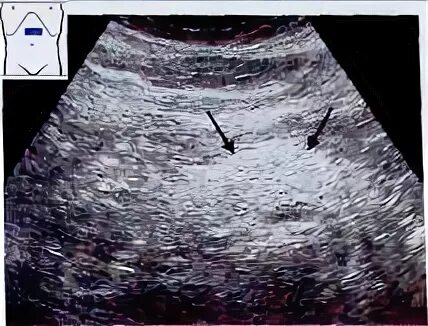

Что значит по типу липоматоза